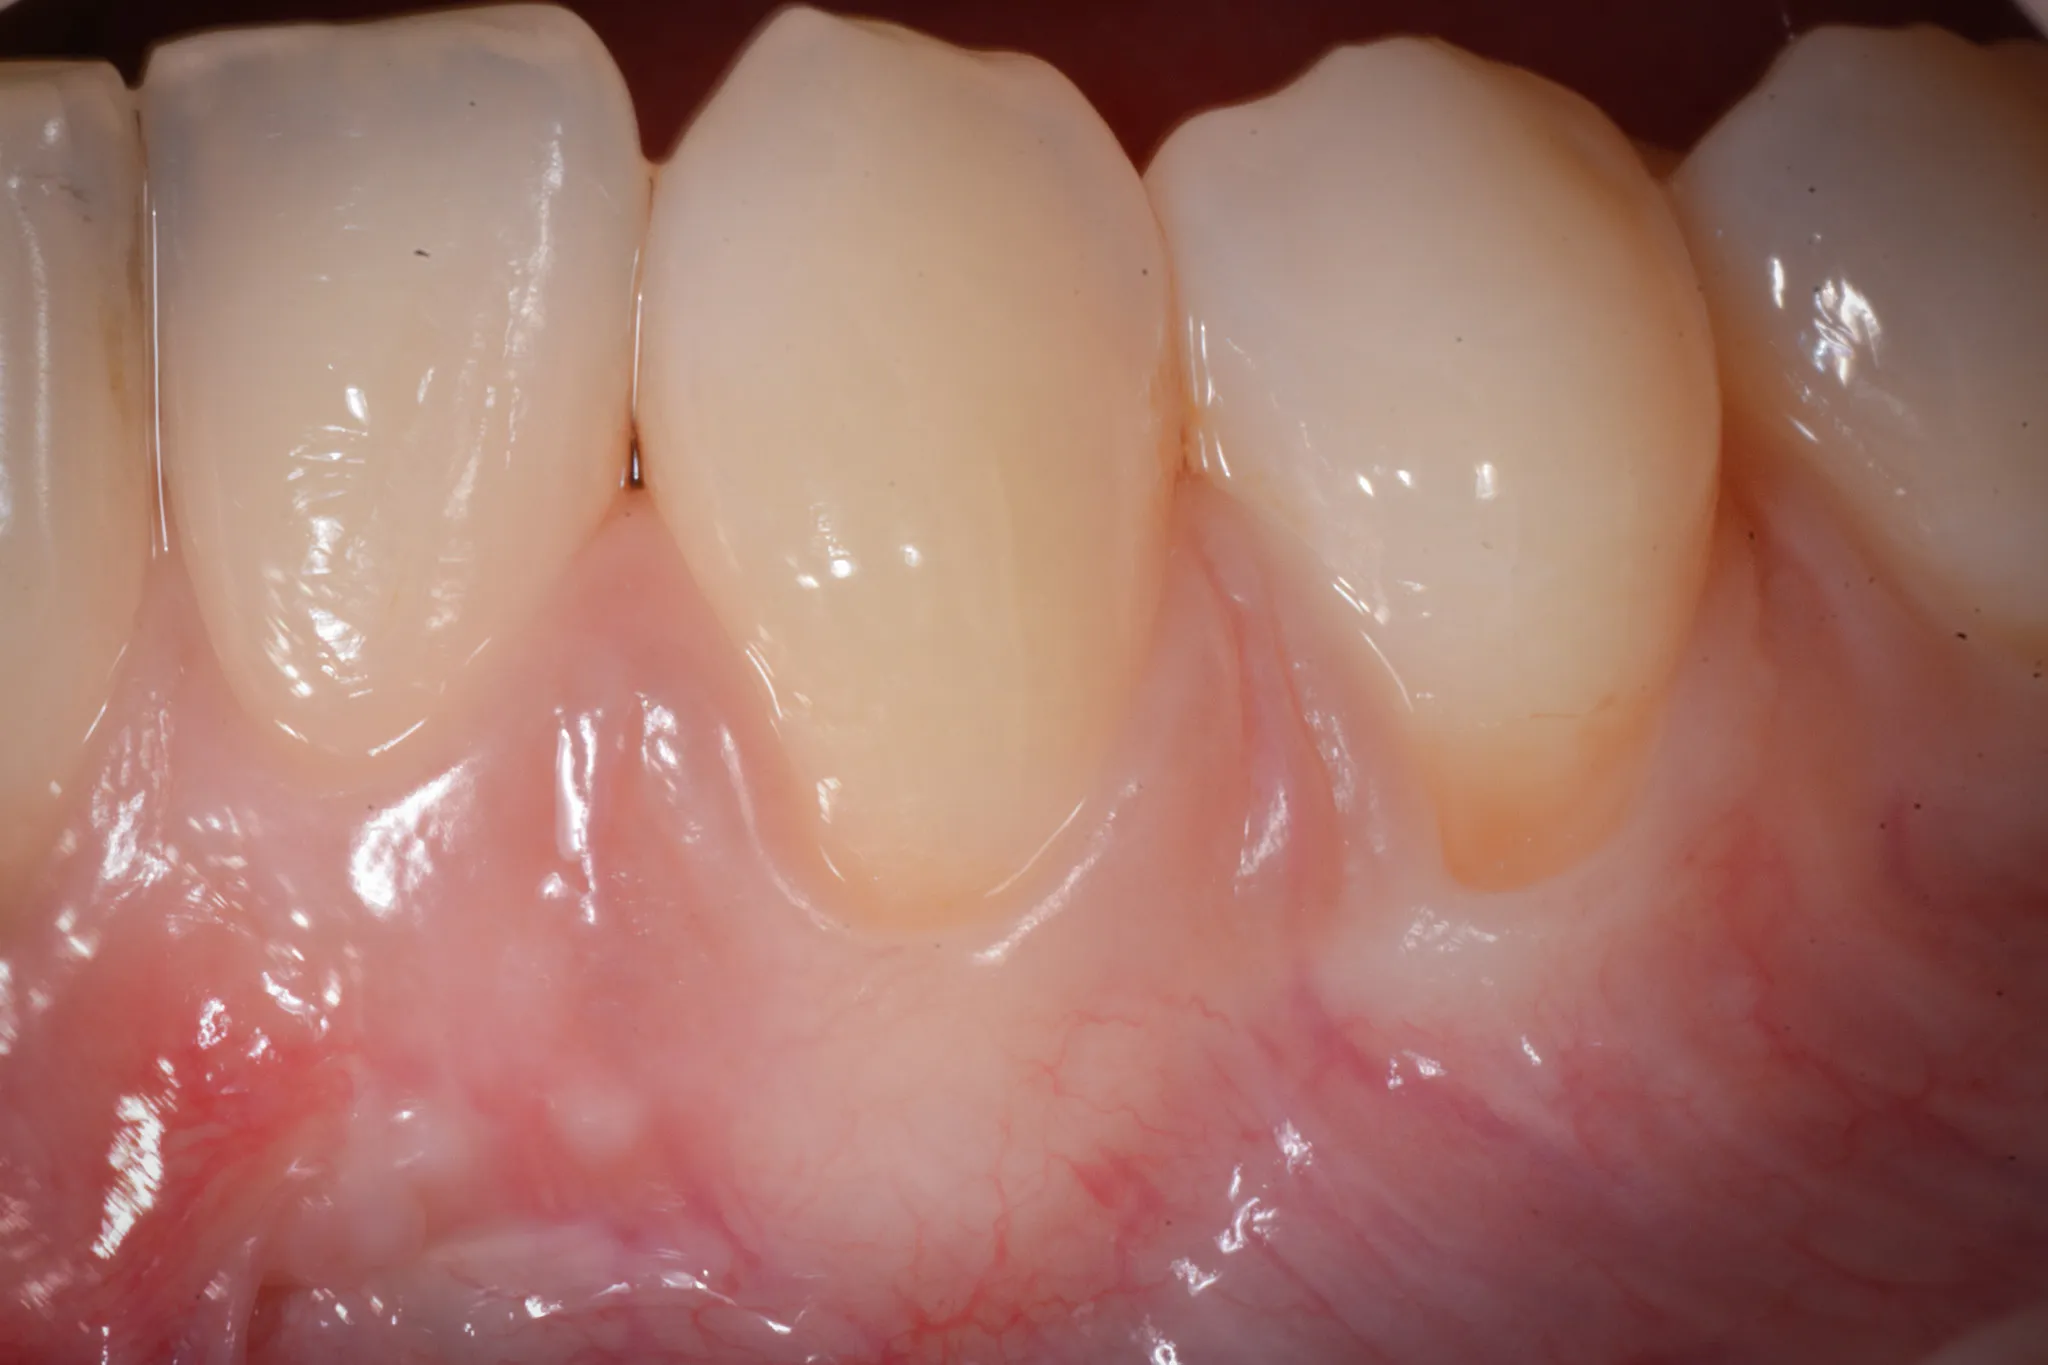

Il tessuto gengivale vero è un tessuto connettivo rivestito da epitelio cheratinizzato (in sostanza, un tessuto più spesso e resistente adeso all’osso sottostante). Quando si ritira, espone la radice del dente — una superficie che non è progettata per stare a contatto con l’ambiente orale. La radice è più porosa dello smalto, più vulnerabile alla carie, più sensibile agli stimoli termici.

Inoltre, a volte la gengiva si assottiglia per vari motivi lasciando spazio da un tessuto più delicato (mucosa orale) che è identico a quello che riveste le guancie e l’interno delle labbra.

RT1 — Recessione senza perdita di attacco interprossimale. L’osso tra i denti è integro. È il caso ideale: la copertura radicolare completa è altamente predicibile.

In parole più semplici: se il livello dei tessuti interdentali è ancora conservato, il chirurgo può riportare la gengiva dove era. Se l’osso tra i denti non c’è più, il risultato sarà parziale ma migliorativo.